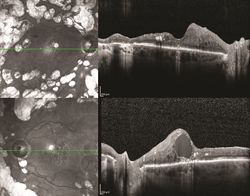

Figure 1. OCT of a patient with bilateral proliferative diabetic retinopathy with diabetic macular edema in the left eye. ©ASRS Retina Image Bank, May 2016. Image 26525. Olivia Rainey, Retina Specialists of Michigan.

An optical coherence tomography (OCT) test provides highly detailed cross-sectional images of the retina that show its thickness, helping determine whether fluid has leaked into retinal tissue.